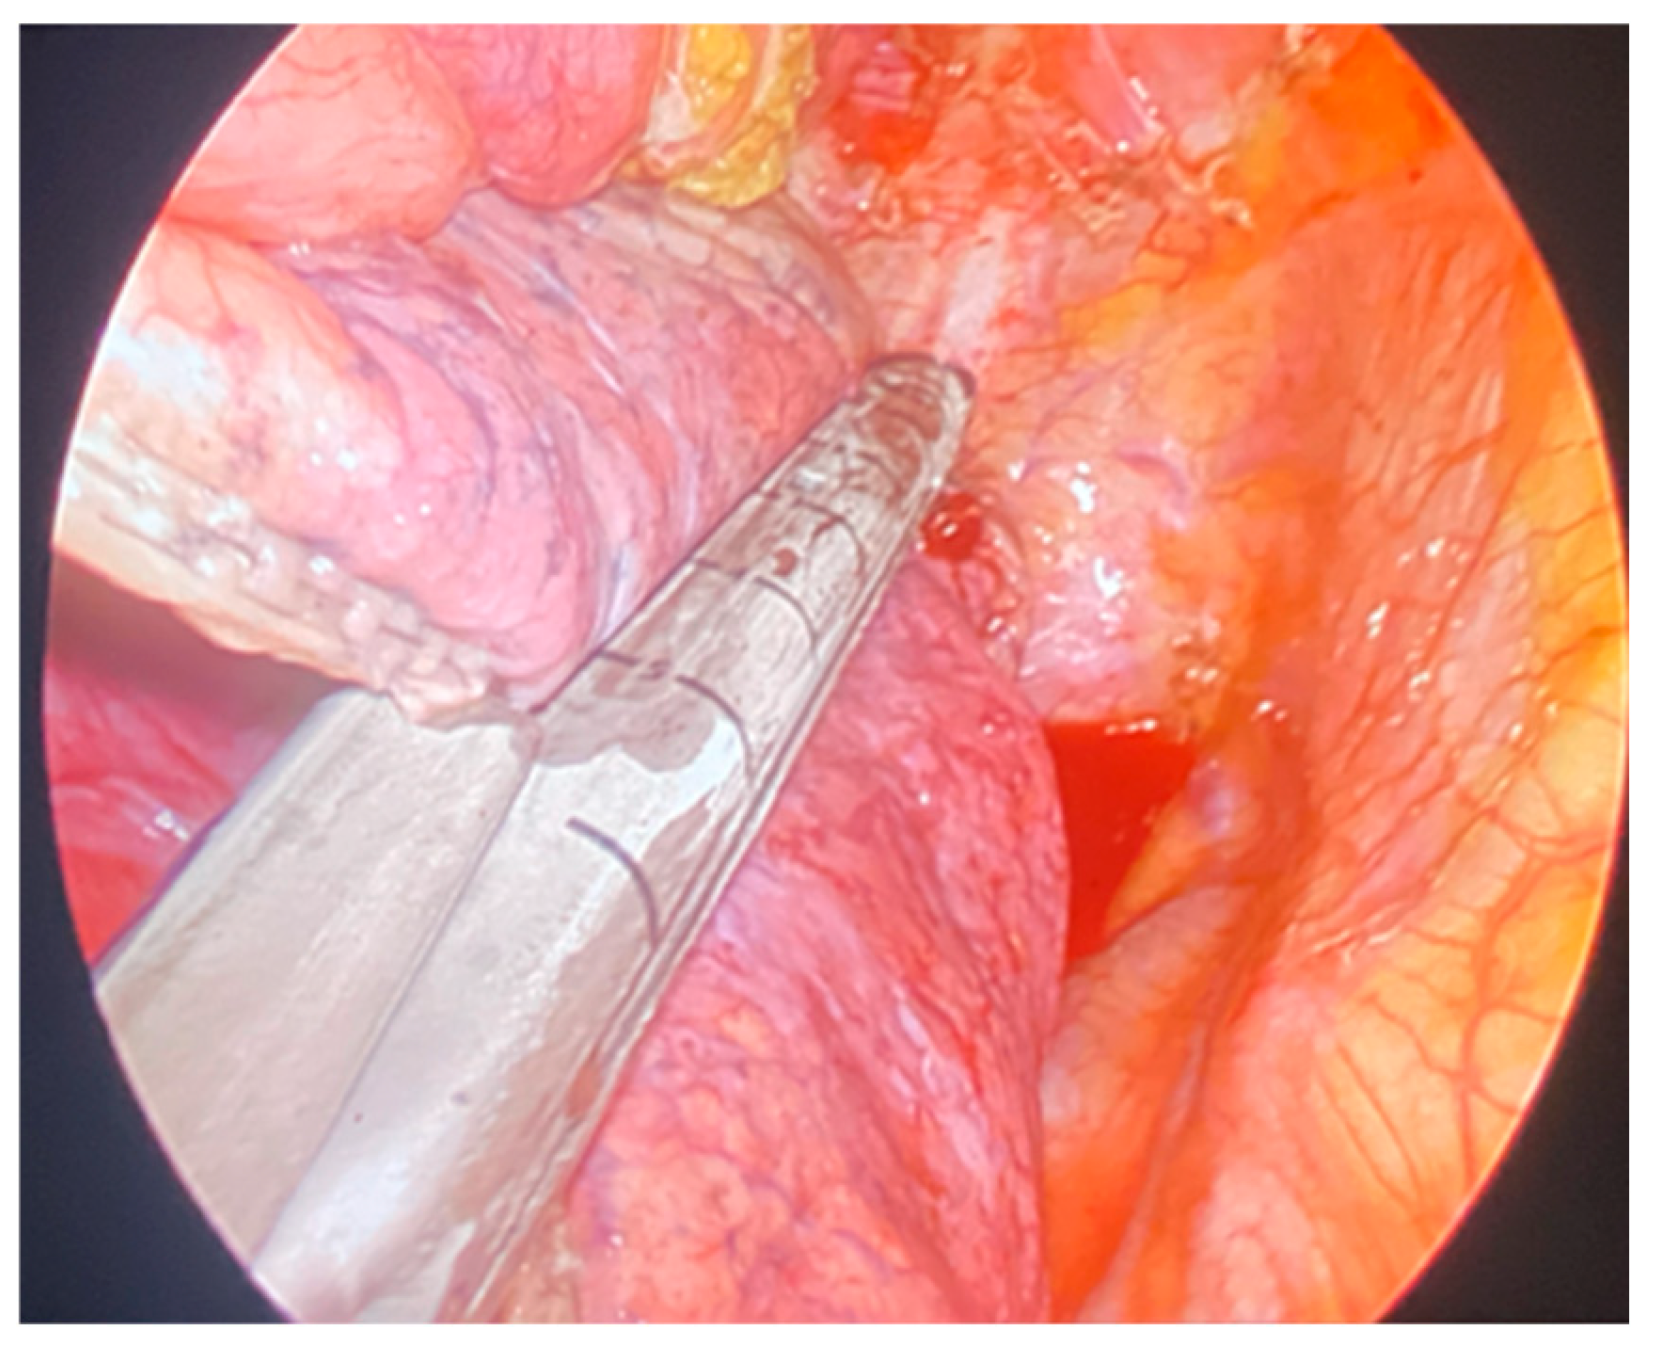

A single 3-cm incision at the 5th intercostal space was performed along the middle axillary line, serving as the exclusive access point for both visualization and instrumentation. A wound protector (Alexis® Small) was used to protect the intercostal space, minimize trauma, and prevent lens contamination of the camera (30°/10 mm) during the procedure. Dedicated long and curved instruments with double articulation, proximal and distal, were used to enhance maneuverability and ensure precise handling of lung tissue within the pleural cavity through the single incision [12,13]. The bullectomy was performed (Figure 1) using staplers with 45- or 60-mm cartridges. In cases of large bullae, especially in patients with severe lung emphysema and fragile pulmonary tissue, where there was a heightened risk of post-operative air-leaks, additional reinforcement of the stapler line was performed. This was achieved by using Gore® Seamguard® bioabsorbable reinforcement (Video S1, Figure 2), a synthetic buttressing material designed to enhance sealing, reduce staple line dehiscence, and minimize the likelihood of persistent air leaks. Additionally, for patients at high risk of pneumothorax recurrence, selective apical chemical pleurodesis was performed. A sterile talc powder was introduced into the pleural spaces via a catheter and distributed evenly.

Figure 1. Extensive wedge on giant bulla of right upper lobe.